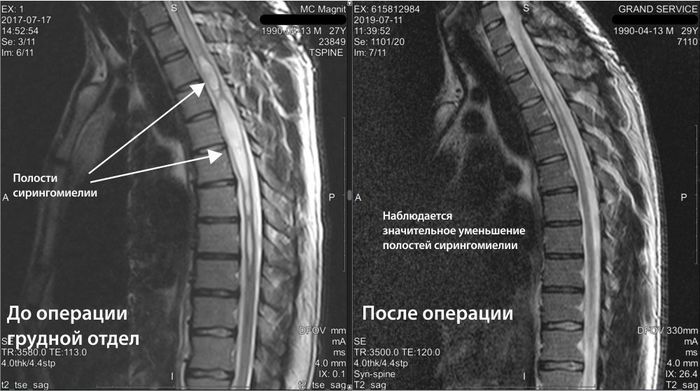

Во время операции выяснилось: у Оли врожденная аномалия сосудов — артериовенозная мальформация. Именно она стала причиной катастрофы. После операции девочка провела три дня в коме, а после — две с половиной недели в реанимации.

Но оставалась главная угроза: мальформация сосудов имела аномальные размеры, поэтому Оле сделали ещё одну операцию. Она прошла успешно. Но в феврале этого года семью ждал новый удар: у Оли случился эпилептический приступ. Оказалось: новая мальформация. В конце марта Оле сделали третью операцию. И после неё Оля снова растеряла все навыки, которые с таким трудом смогла вернуть.